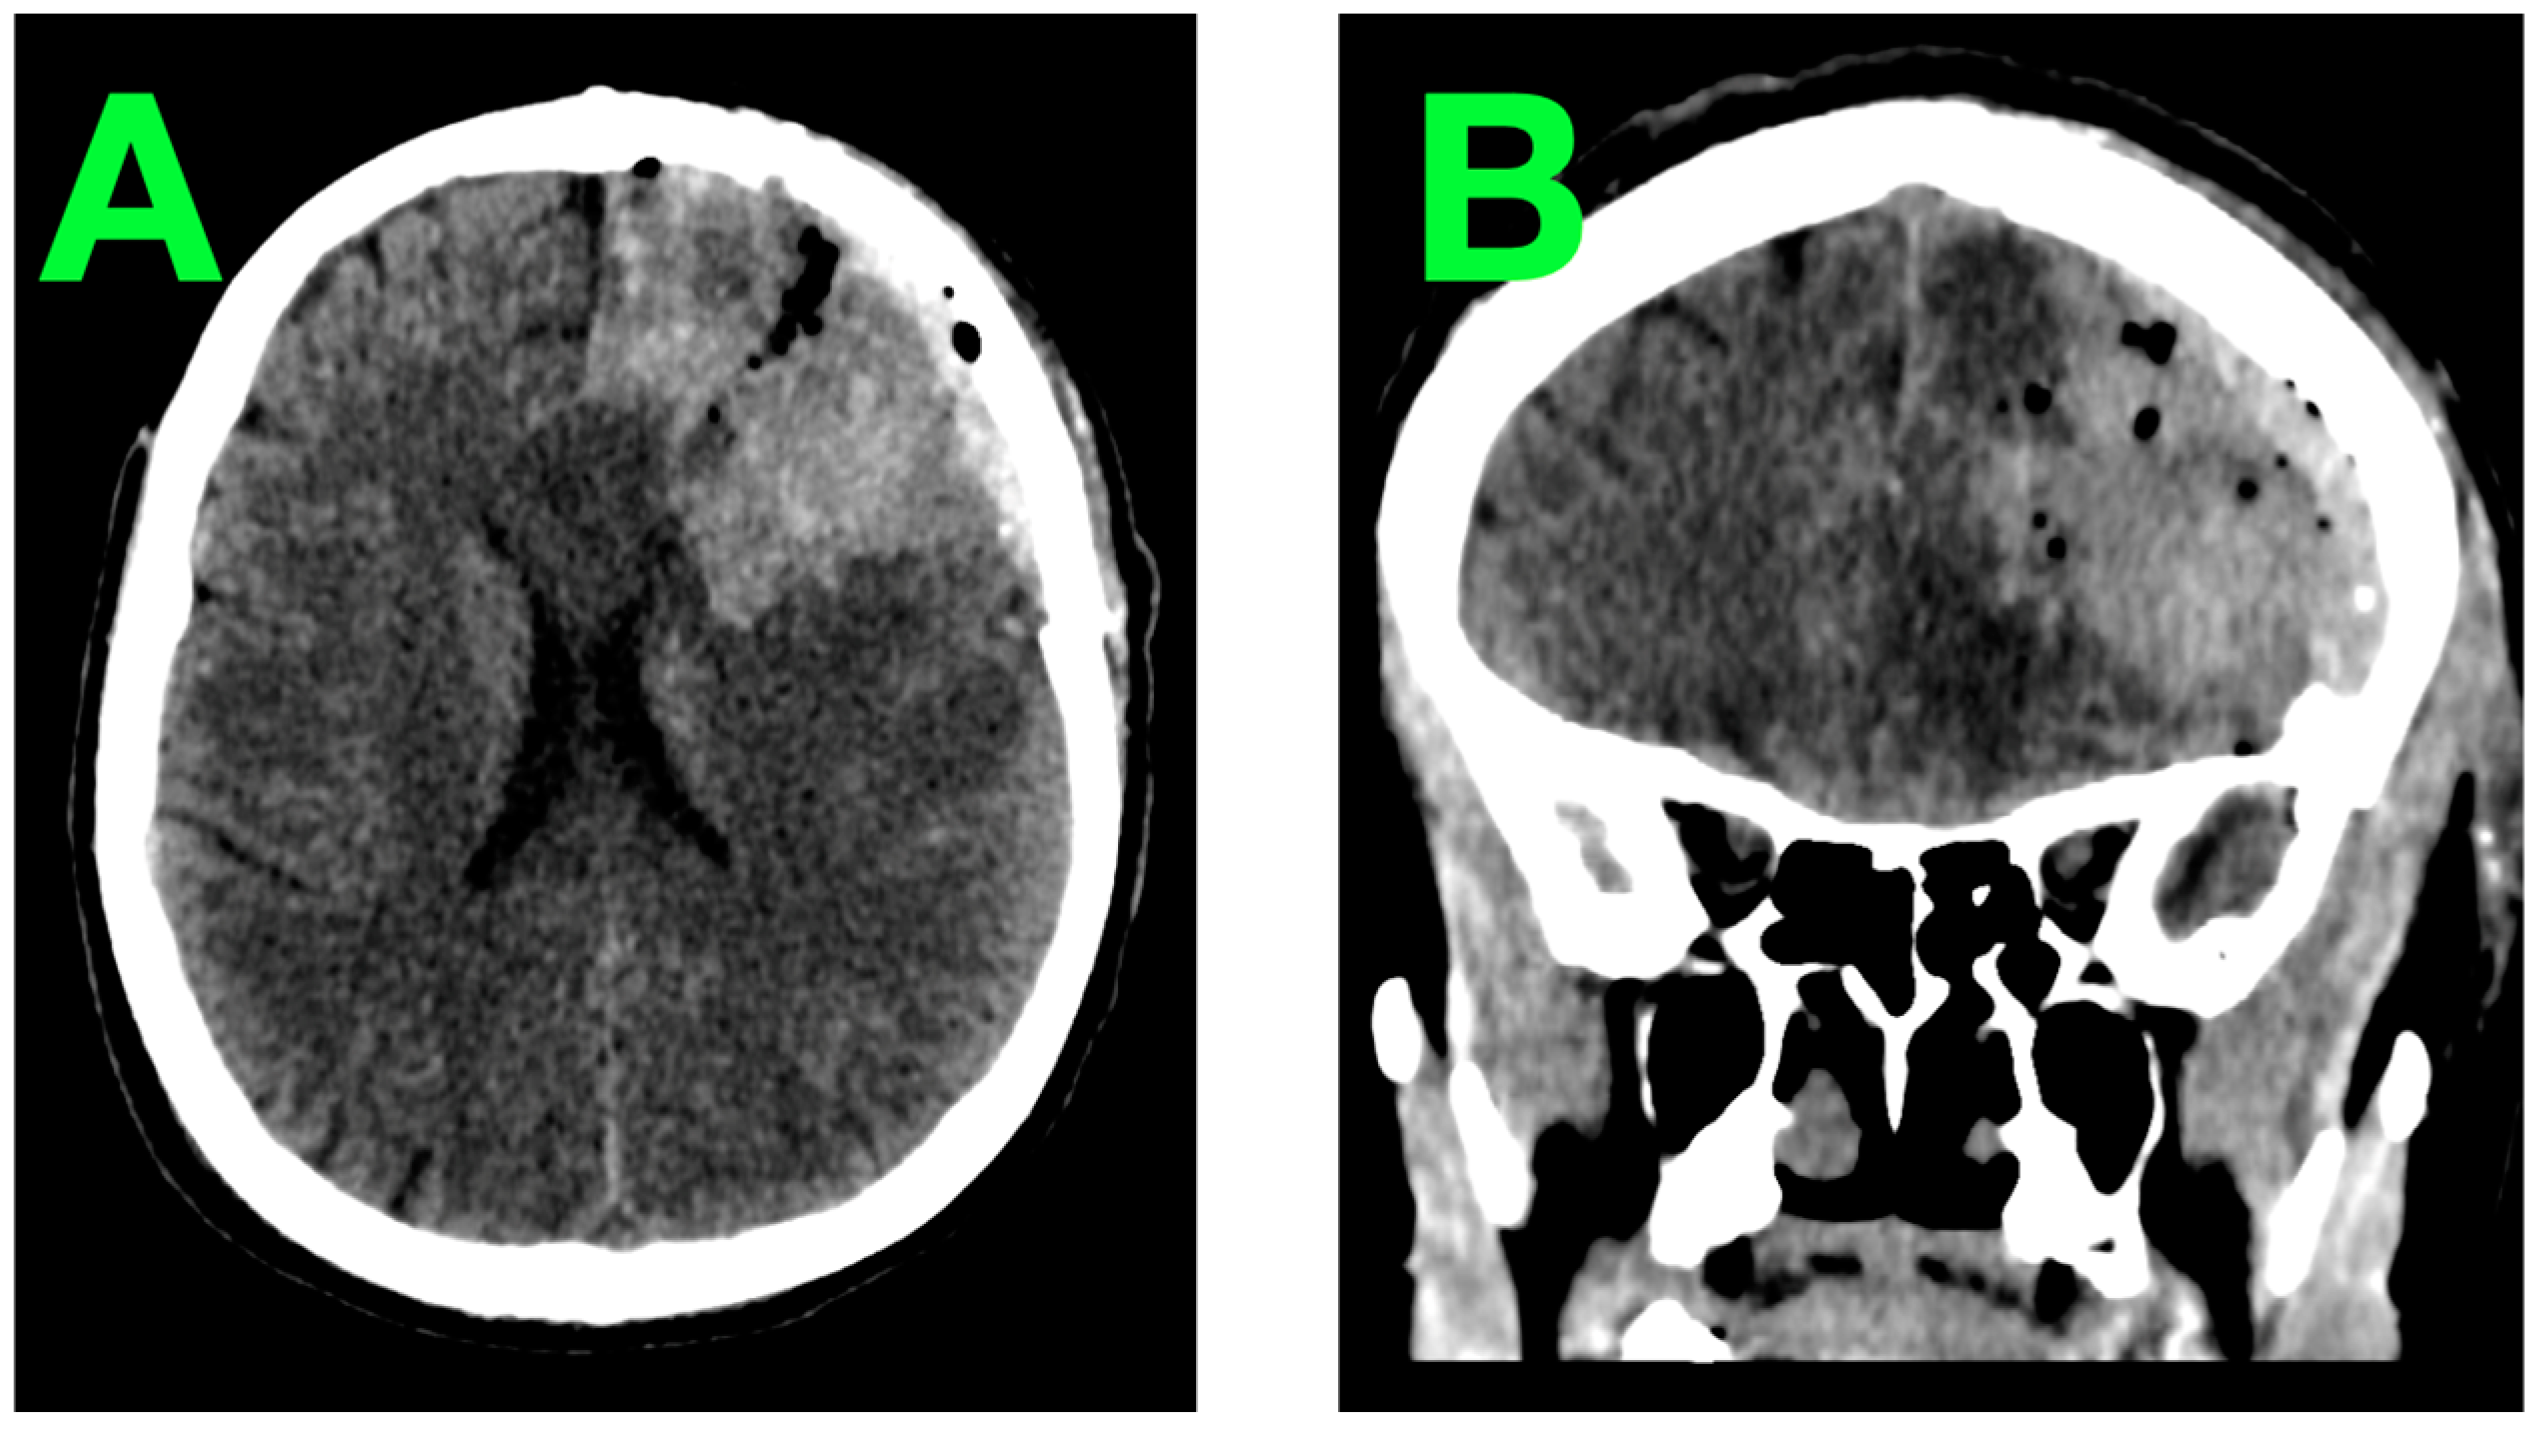

2.2. Diagnostic Workup

2.6. Initial Imaging and Clinical Monitoring